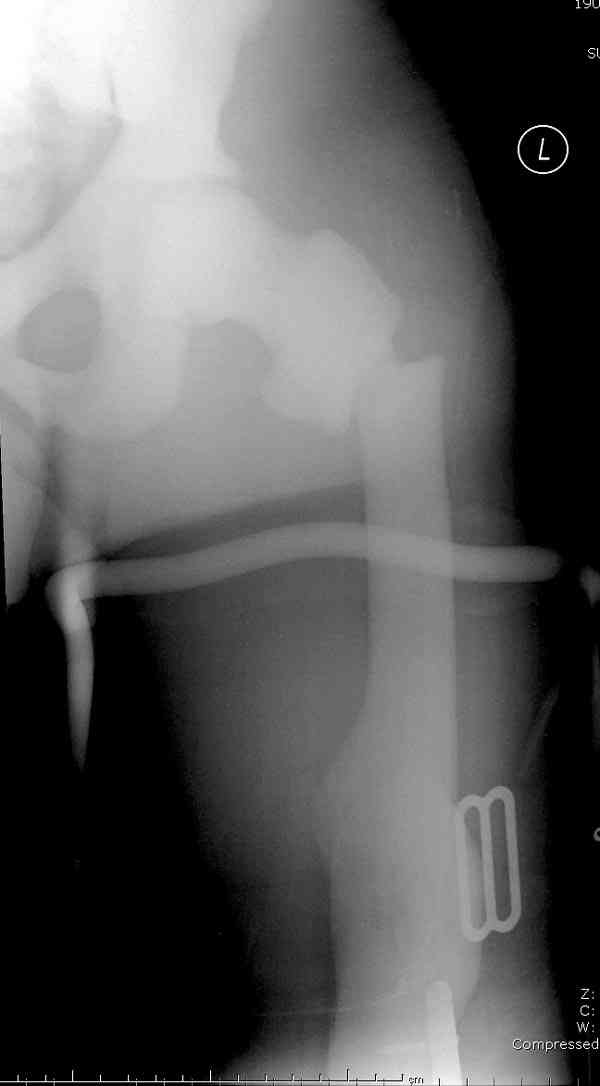

Не являюсь специалистом по костной патологии, но мне кажется, на

ренгенограмме множественные мета-диафизарные образования напоминяющее

змееподобных извилистых линии и периостеальные ламинирование очень

напоминяет картину остеонекроза (инфаркта) костей, возможно связано с

длительным применением стероидов.

на снимке слайд из прошлегодного случая.

Вложение не в текстовом формате было извлечено…

Имя     : smith distalfemur lat.jpg

Тип     : image/jpeg

Размер  : 33812 байтов